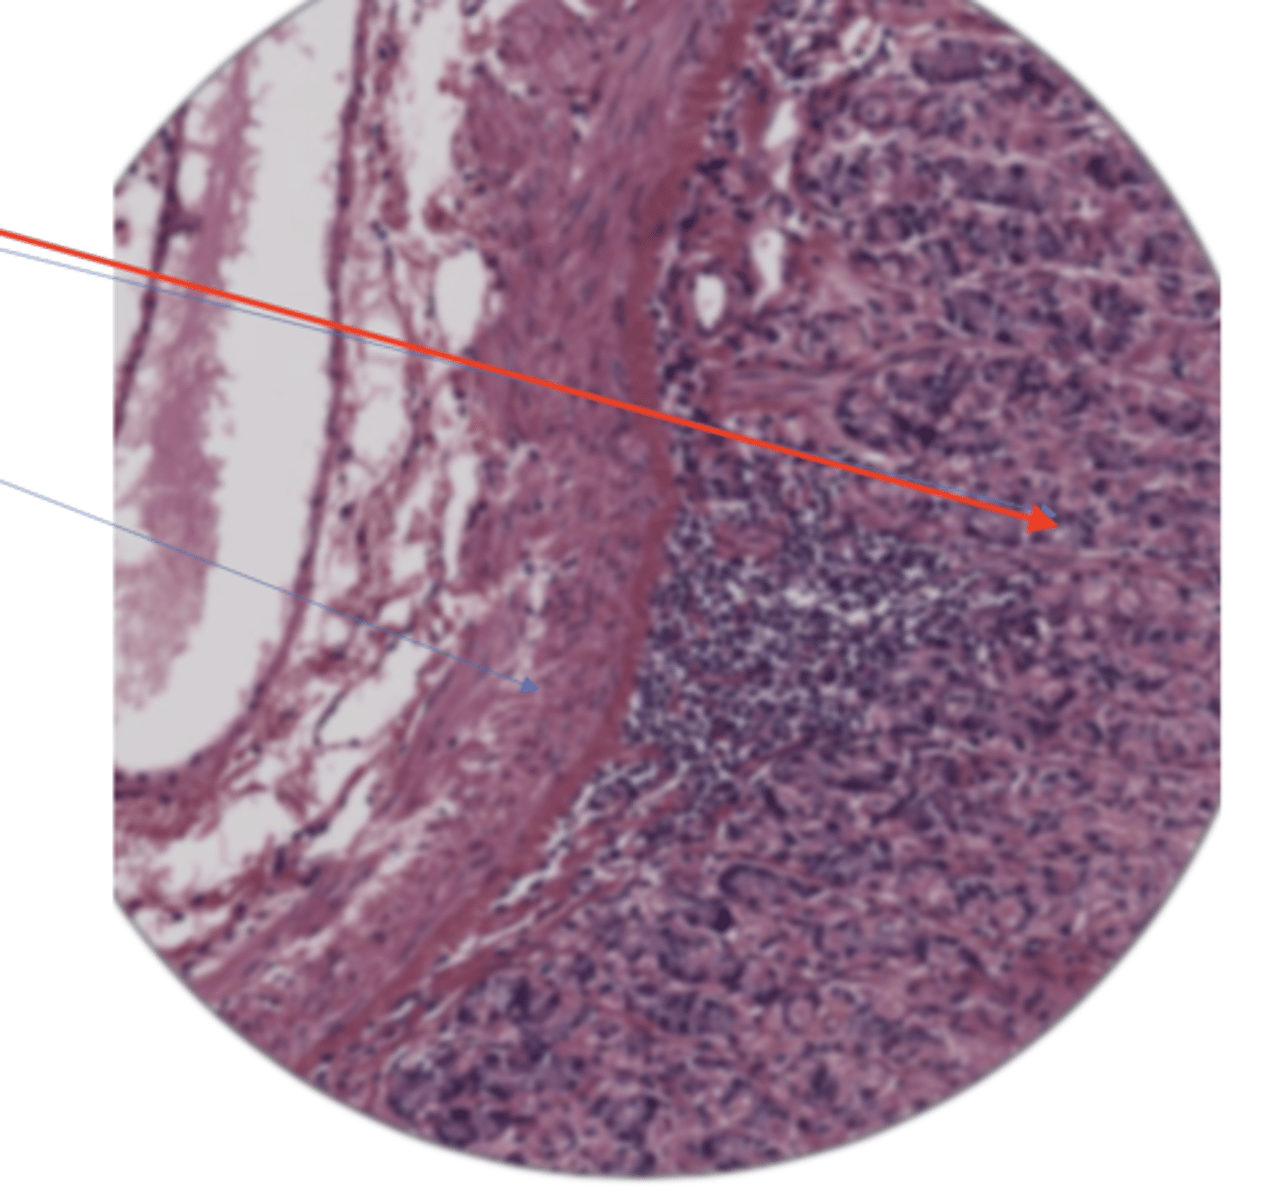

stomach mucosa layer (400)